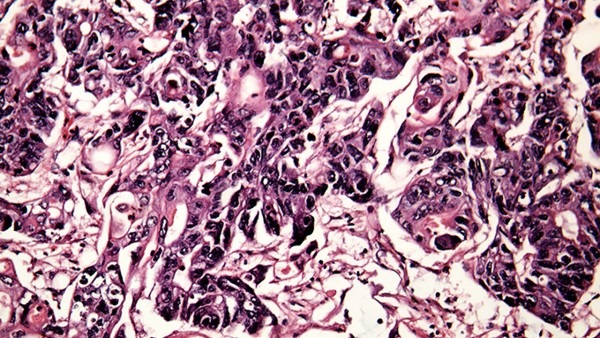

潛伏期過后患者身體開始出現出現明顯病癥,長出淡紅色或污紅色的小丘疹,如果沒有及時治療的話,這些小疙瘩可很快長大,發展為乳頭狀、菜花狀、雞冠狀等形狀的疣體贅生物,表面呈顆粒狀,或呈現濕潤或有出血的情況,這些疣體贅生物可很快破潰,形成潰瘍面。